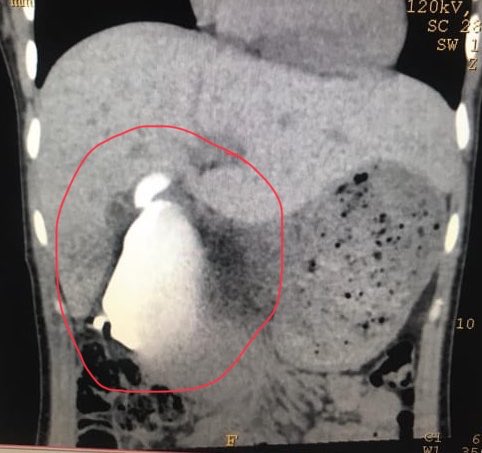

حاولنا بعدها اجراء منظارين للقنوات المراريه لوضع دعامه

و تصريف موقت داخلي لكن فشلنا و ثبت انه لا مجرى مفتوح وانسداد كامل..

بعد ان تشافت المريضه دخلت العمليه الكبيرة و هي استاصال كامل القنوات المراريه خارج الكبد و اعادة تكوين مجرى جديد بتوصيل الامعاء واجريت لها عمليتين الاولى بالمنظار والثانية بفتحه صغيره..